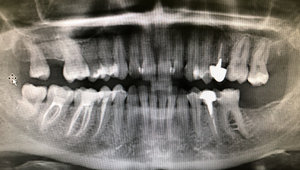

Попала к девушке со стажем работы 1 месяц. Мне удаляли нервы, но не смогли полноценно запломбировать зуб. Только один из каналов вроде запломбировали, т.к. из канала шла кровь, и они не могли её остановить. Прижигали мне там что-то по 10 раз. Поставили временную пломбу, а под нее вату. На следующий день тоже самое, на помощь молодому врачу подключилась врач со стажем. Она посверлила еще и нашла еще один канал. Опять прижигали. Шептались постоянно, я услышала фразу про две перфорации. Послали на рентген. Следующий прием только через 3 дня. К ней точно не пойду, уже нет доверия. Это была стоматология по ОМС. Пойду в платную стоматологию, может, спасут зуб.

Перфорация может быть стенки корня, стенки коронки, верхнечелюстной пазухи и т.д.

По снимку, определить о какой перфорации шептались Ваши врачи, не представляется возможным.